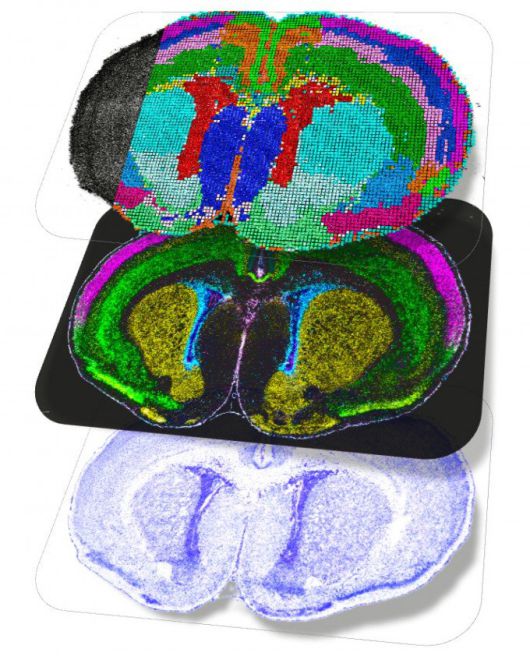

출생 직후 쥐의 뇌 공간 지도. 단백질이나 리보핵산(RNA) 등이 실제로 뇌의 어느 위치에서 상호작용하는지를 보여준다. 네이처 제공 |

인간의 뇌가 발달하는 과정에서 형성되는 세포 유형은 수천 종에 달한다. 세포들은 급속히 변화하기 때문에 과학자들은 정확한 뇌세포 분화 과정을 이해하는 데 어려움을 겪는다. BICAN 연구진은 고해상도 이미지 처리 기술과 첨단 계산 도구 등을 활용해 뇌 발달 과정에서 뇌세포 유형이 어떻게 출현하고 다양화·조직화되는지 추적했다.

앨런연구소 연구팀은 쥐의 뇌 발달 초기부터 청년기까지 77만 개 이상의 개별 세포를 추적해 대뇌 시각 피질 내 모든 세포 유형의 발달 과정을 기록했다. 그 결과 기존 예측과 달리 뇌세포가 출생 후에도 발달을 활발히 이어간다는 사실이 발견됐다. 눈을 처음 뜨는 순간이나 뇌가 시각 정보 처리를 배우기 시작하는 순간과 같은 중요한 시점을 중심으로 청소년기까지 새로운 세포 유형이 지속적으로 형성된다는 것이다. 출생 후 겪는 경험이 뇌의 신경회로 구축에 영향을 미치는 비중이 기존 예상보다 크다는 의미로, 출생 이후 발달장애 치료 가능성을 확인한 것으로 평가된다.